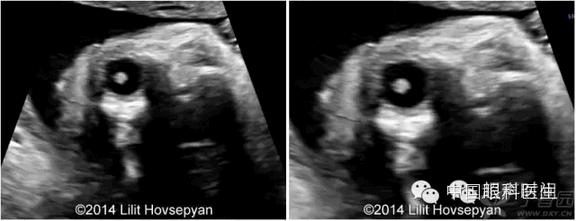

图 1 和图 2 均为胎儿面部冠状切面,其眼球内可见强回声晶状体

病例 2. 患者 22 岁,G1P0,无明显个人病史和家族病史,其孕 22 周首次超声检查未见异常。孕 34 周时因怀疑巨细胞病毒感染合并严重宫内发育迟缓以及羊水过少和脑室轻度扩张和双侧白内障来我处就诊。